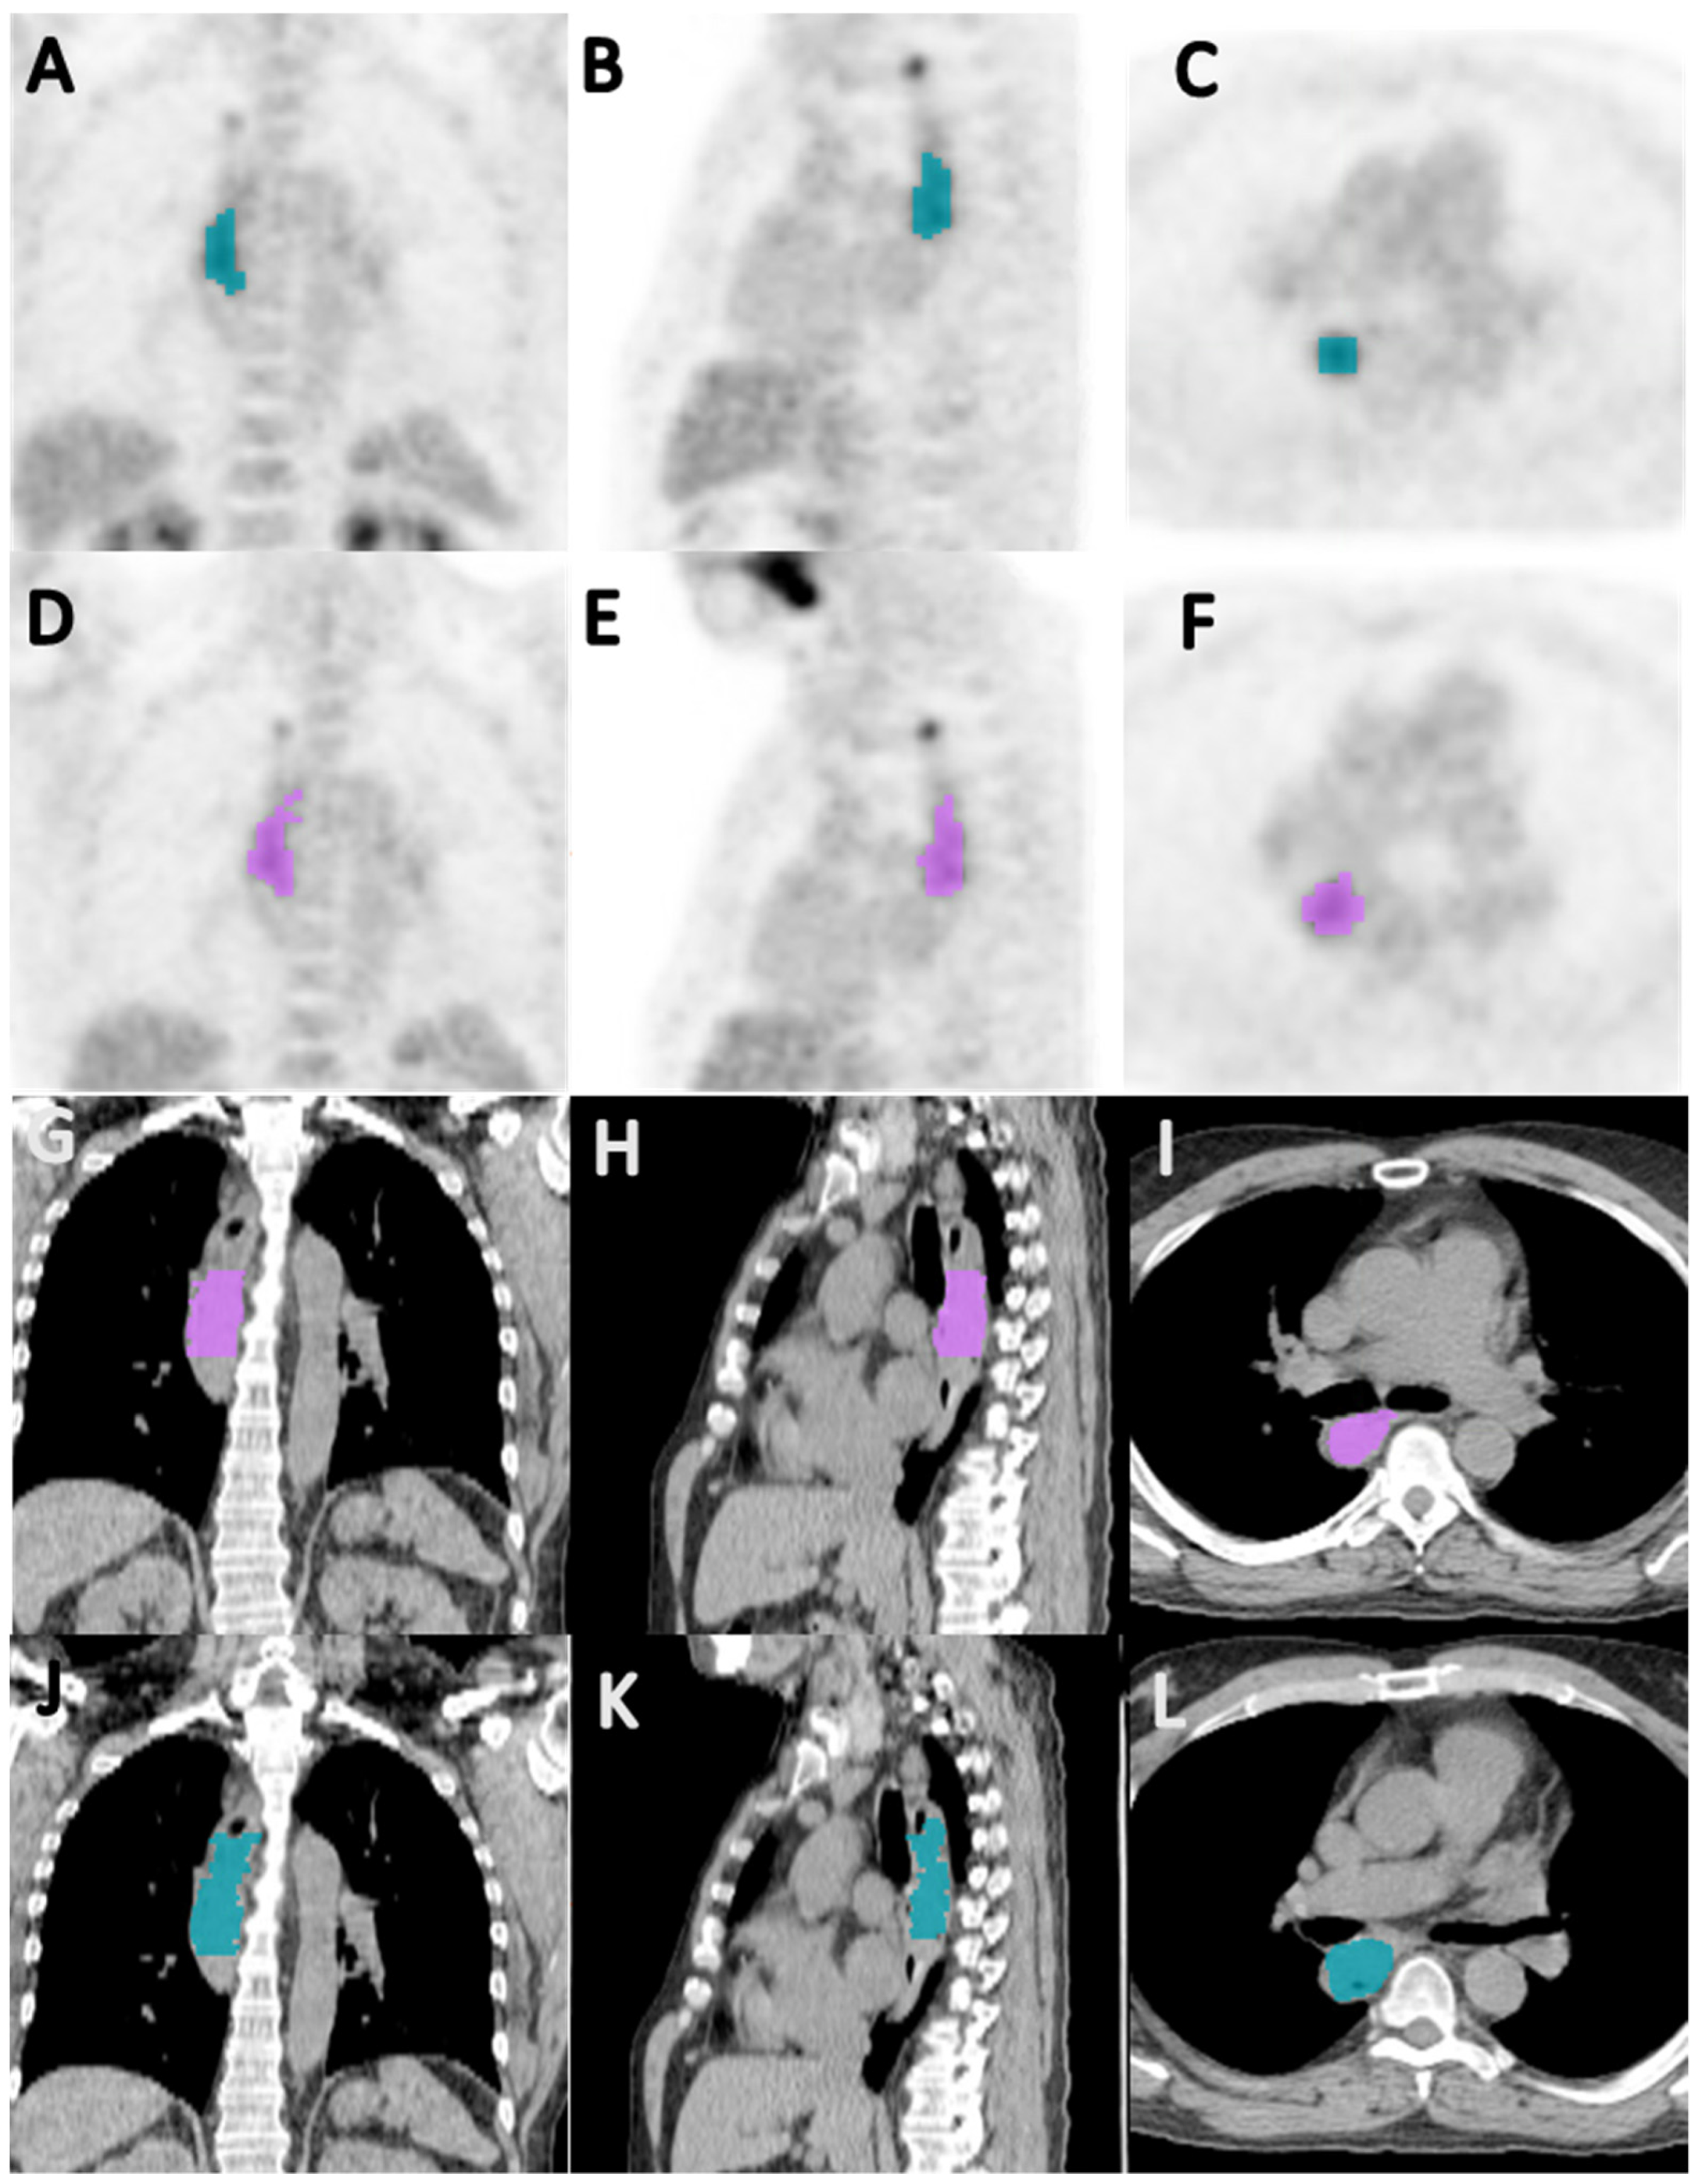

2.3. Image Acquisition and Segmentation

2.4. Radiomics Analysis